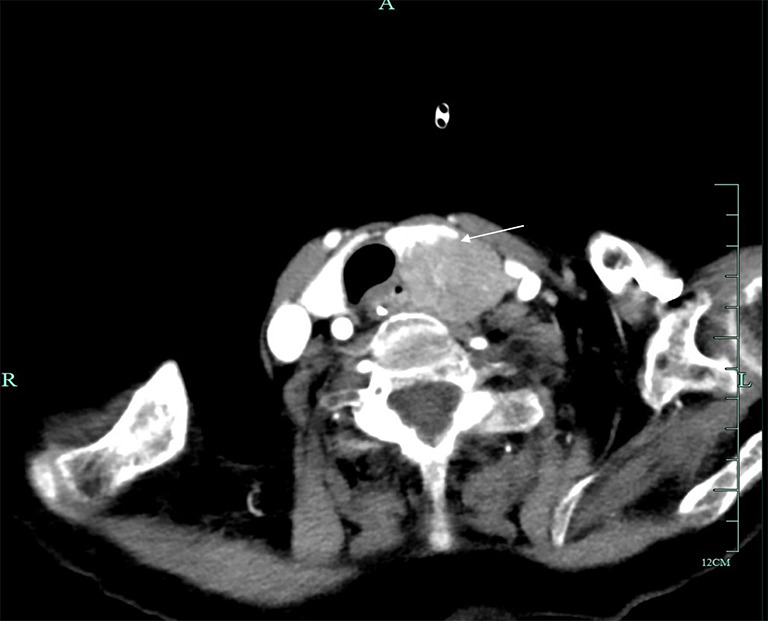

背景:甲状旁腺癌是一种罕见的内分泌恶性肿瘤。大多数病例为功能性甲状旁腺癌,而极少数为非功能性甲状旁腺癌。非功能性甲状旁腺癌患者的预后通常比功能性甲状旁腺癌患者差。这通常是由于非功能性甲状旁腺癌的隐匿性,通常导致较晚的发现和诊断。病例描述:2011年5月至2022年11月,浙江大学第一附属医院对6例诊断为甲状旁腺癌的患者进行了手术治疗。其中2名男性,4名女性,年龄从53岁到83岁不等。2例肿瘤位于右颈,4例肿瘤位于左颈。最小的肿瘤直径为2.5厘米,而最大的肿瘤直径为11.4厘米。2例为异常罕见的非功能性甲状旁腺癌,4例为功能性甲状旁腺癌。所有6名患者都接受了手术。病理类型包括主细胞型2例,混合细胞型2例,嗜氧细胞型1例,透明细胞型1例。随访时间为1 ~ 151个月。5名患者存活,1名患者死亡。无功能甲状旁腺癌患者均有复发和转移,Ki-67水平分别为30%和20%。相比之下,4例功能性甲状旁腺癌患者均无复发,1例Ki-67水平为20%,3例Ki-67水平为5%。结论:非功能性甲状旁腺癌患者预后不良可能反映了其生物学行为和较高的恶性潜能。Ki-67水平与甲状旁腺癌的恶性潜能呈正相关。这些推测仍然需要通过大规模的临床研究来验证。

Case description: Between May 2011 and November 2022, the First Affiliated Hospital of Zhejiang University conducted surgical treatment on six patients diagnosed with parathyroid carcinoma. Of these, two were male and four were female, with ages spanning from 53 to 83 years. The tumors were situated on the right neck in two cases and on the left neck in four cases. The smallest tumor measured 2.5 cm in diameter, whereas the largest measured 11.4 cm. Two cases were exceptionally rare nonfunctional parathyroid carcinomas, and four were functional parathyroid carcinomas. All six patients underwent surgery. Pathological types comprised the chief-cell type in two cases, the mixed-cell type in two cases, the oxyphil-cell type in one case, and the clear-cell type in one case. The follow-up duration ranged from 1 to 151 months. Five patients remained alive, while one patient died. Both patients with nonfunctional parathyroid carcinoma experienced recurrence and metastasis, with Ki-67 levels of 30% and 20%, respectively. In contrast, none of the four patients with functional parathyroid carcinoma recurred, with one case having a Ki-67 level of 20% and three cases with a Ki-67 level of 5%.